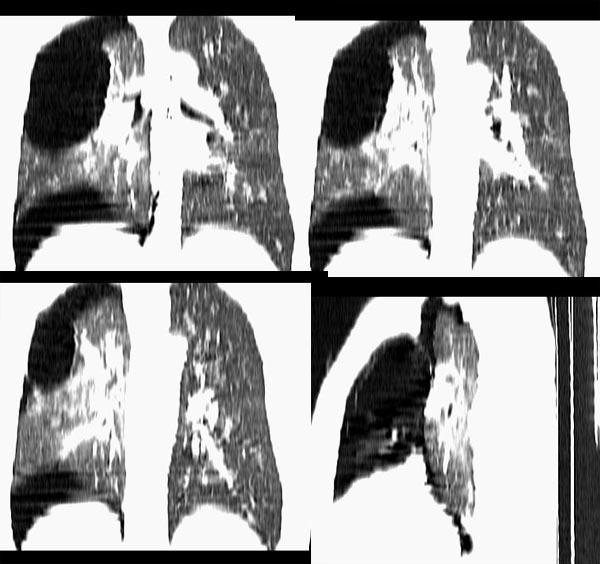

m21y既往体健,否认结核、支扩等病史;1周前患上感,无明显咳嗽,自觉无明显不适。单位体检透视时发现右侧液气胸!cr及ct如下(肺组织窗:l:-598hu w:1132hu):请大家会诊!!

右侧巨大含气囊性病变,壁薄、光整、其外侧见气体。右肺压迫性肺不张、胸腔内见少量积液。纵隔向左侧移位。左肺未见异常。诊断:1.右侧含气肺囊肿(先天性)。2.右侧液气胸。(少量液体)3.右肺压迫性肺不张。我也遇见一例这样的病人。女性。股骨外伤就诊。常规胸片发现右侧囊性病变。

本例病史无胸闷、气短等症状;影像学示气囊壁厚,病变区透亮度介于气胸与肺大皰之间,内无发丝样阴影,不伴有周围肺气肿;囊肿位于肺表面。壁厚,张力不高,在游离、切除过程中并不破裂,可与肺大皰相区别。另外,病人有长期吸烟史,每日30余支,术中却见肺表面如同正常小儿肺,无炭末、粉尘沉积,因此,该病可能为自幼存在的先天性疾病。